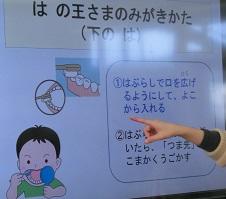

11/28 歯磨き指導5

6歳臼歯をテレビで映します。

虫歯になるとこんなふうになってしまいます。

これが6歳臼歯です。このようにくぼんでいるので子供には磨くのが特に難しい歯なのです。

ですから今回は奥歯を上手に磨く磨き方をならいました。